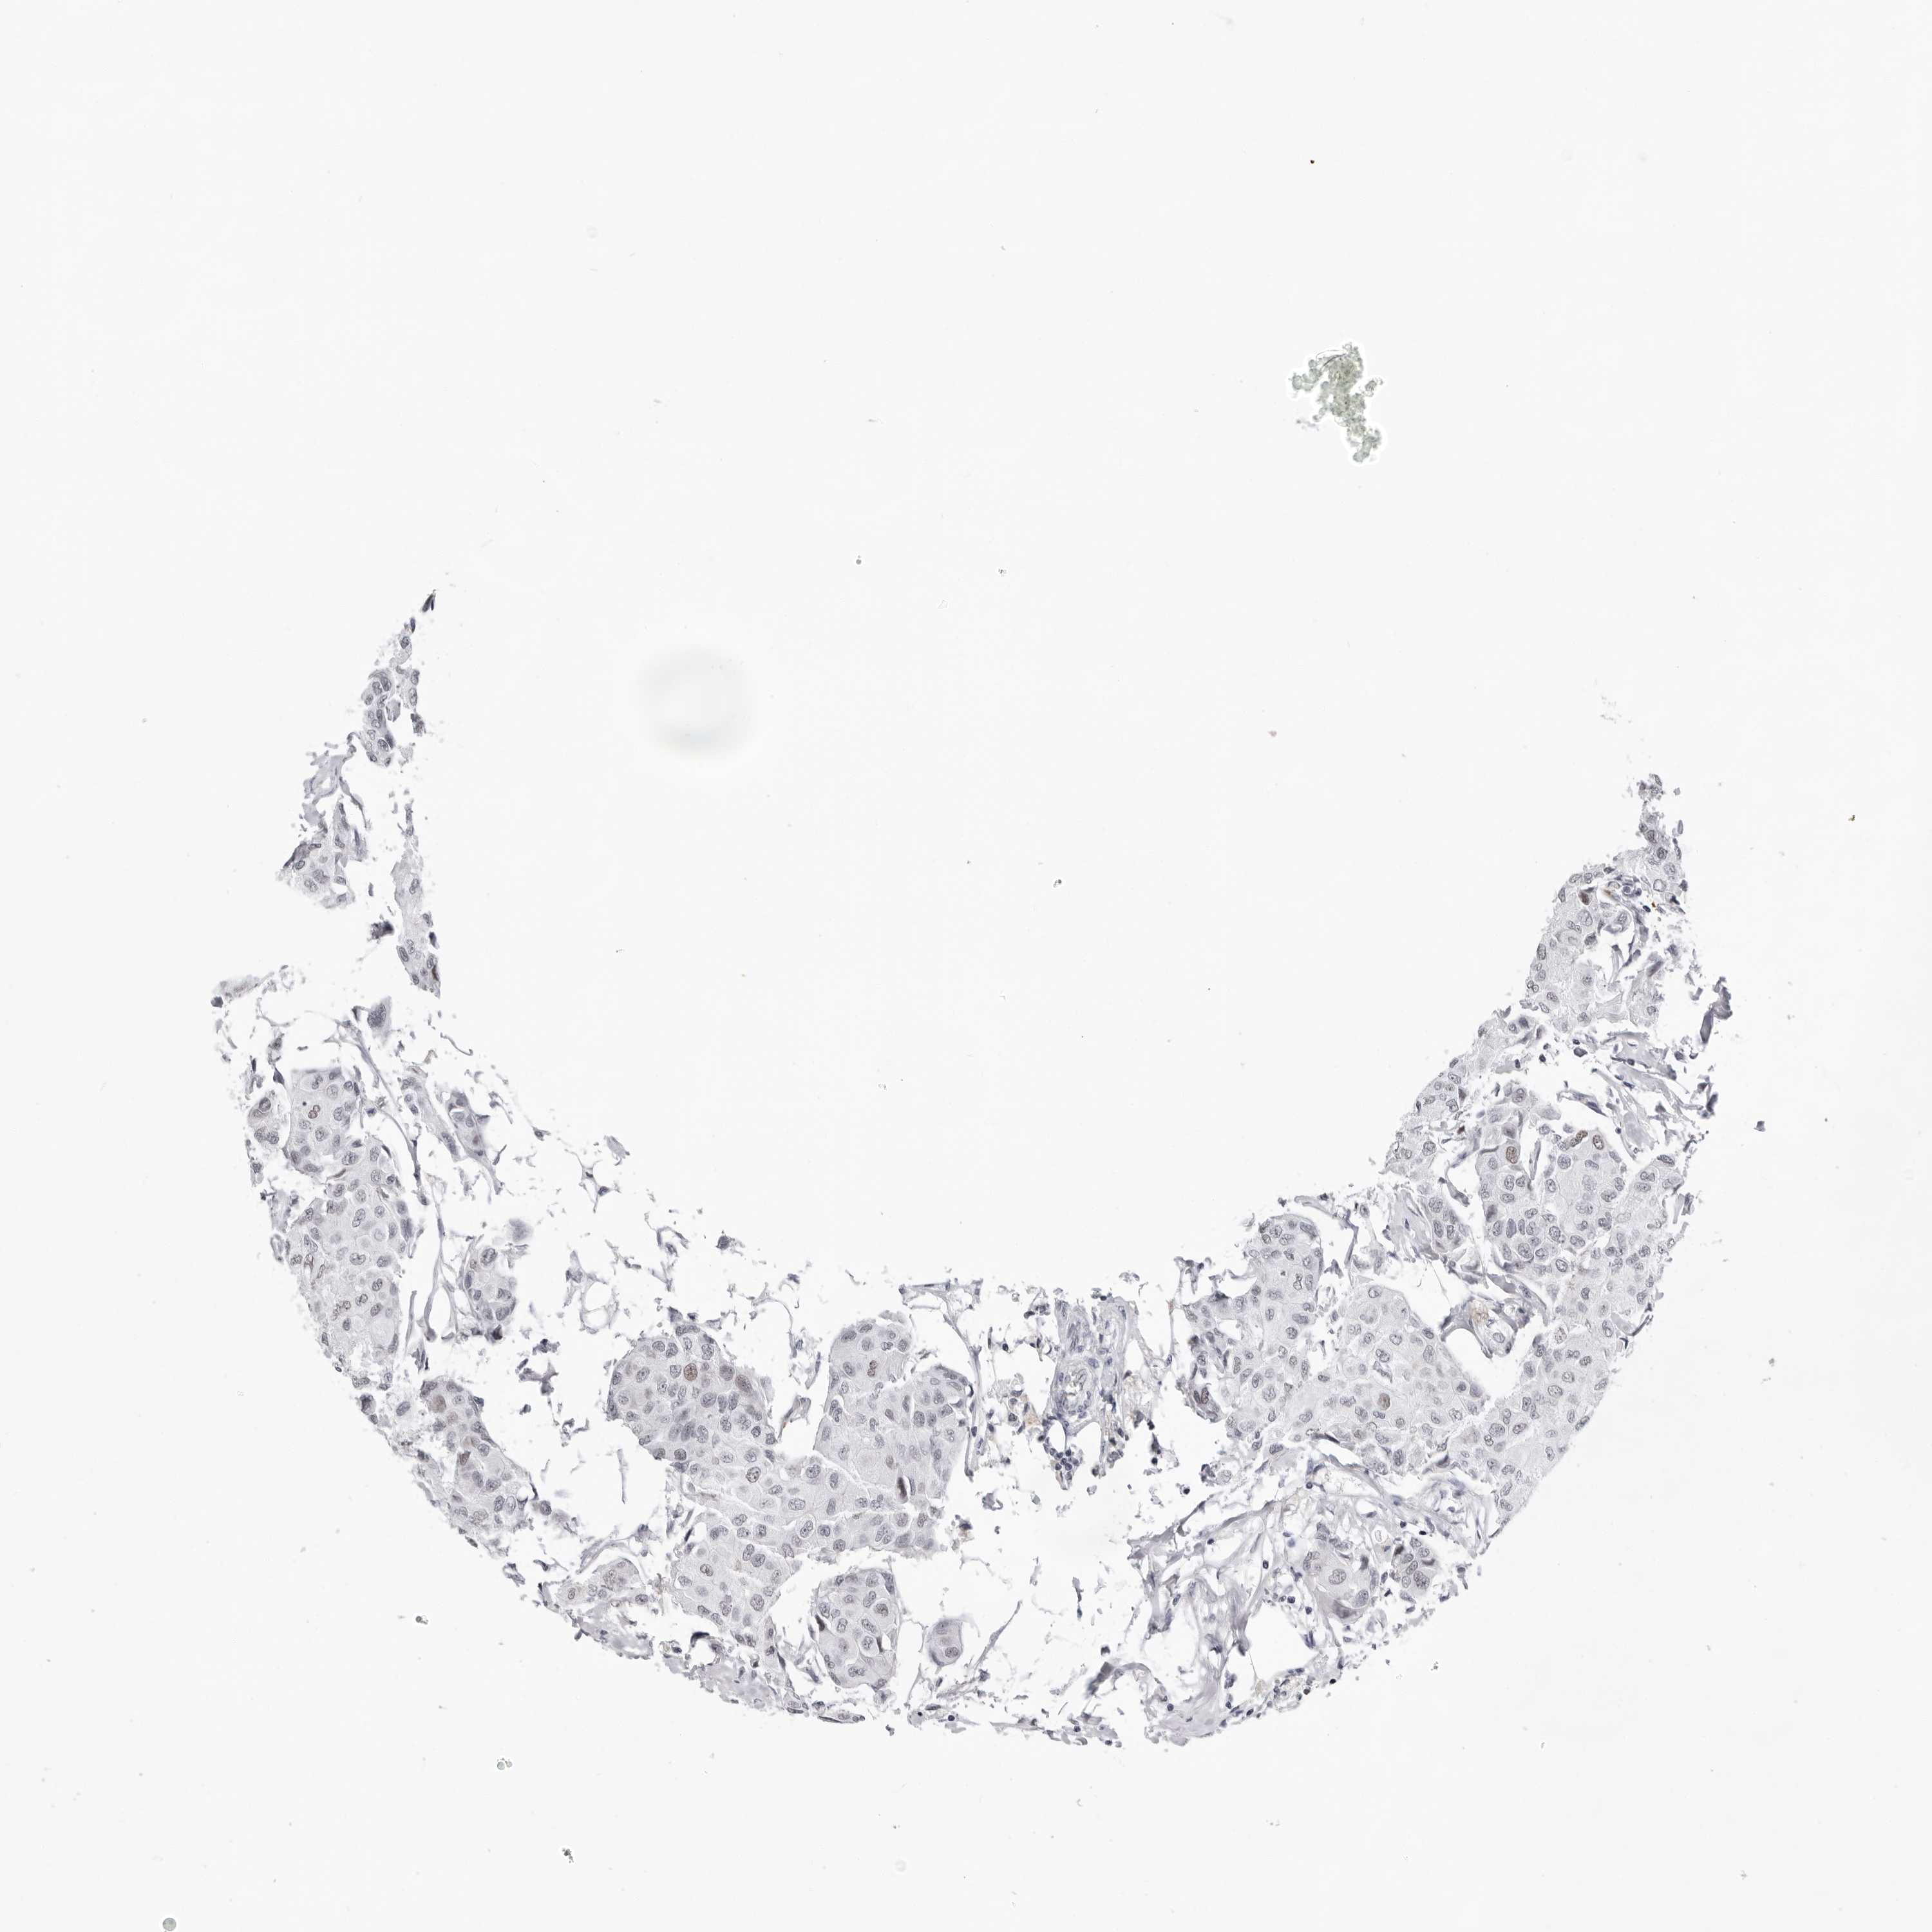

BRCA TCGA BRCA VALIDATION PROTEIN EXPRESSION

ANTIBODIES

AND

VALIDATION